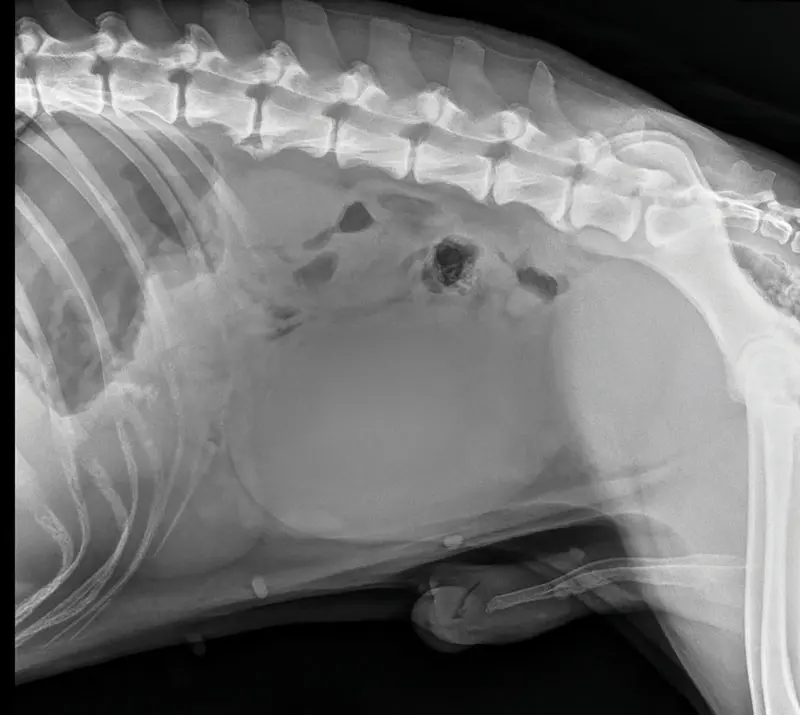

Brain Teaser: Can you solve this puzzle?February 17, 2026Test your veterinary knowledge with our monthly challenge, featuring a three-year-old male intact Beauceron presenting for six hours of lethargy, non-productive vomiting, and restlessness.